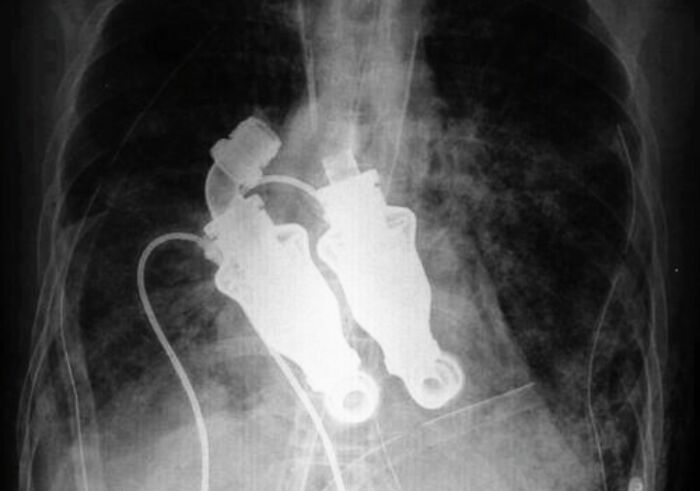

Doctors From The Texas Heart Institute Have Performed A Surgery Implementing A Device That Left A Man Becoming The World's First Heartless Human Leaving Him Without A Pulse Or Detectable Heart Beat